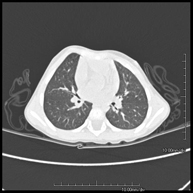

- Tórax- TC Tórax Prueba diagnóstica que consiste en obtener imágenes del tórax de alta definición anatómica (pulmones, corazón, mediastino, grandes vasos, caja torácica, etc.) mediante el empleo de un equipo de TC (Tomografía Computarizada). Dichas imágenes se estudian posteriormente en una estación de trabajo que permite reconstrucciones bidimendionales en diferentes planos del espacio y también reconstrucciones 3D (volumétricas). Algunos estudios requieren el empleo de contraste yodado para mejorar la definición de las imágenes. Prueba diagnóstica que consiste en obtener imágenes del tórax de alta definición anatómica (pulmones, corazón, mediastino, grandes vasos, caja torácica, etc.) mediante el empleo de un equipo de TC (Tomografía Computarizada). Dichas imágenes se estudian posteriormente en una estación de trabajo que permite reconstrucciones bidimendionales en diferentes planos del espacio y también reconstrucciones 3D (volumétricas). Algunos estudios requieren el empleo de contraste yodado para mejorar la definición de las imágenes.

- TC Tórax alta resolución Prueba diagnóstica que consiste en el estudio del pulmón mediante el empleo de un equipo de TC (Tomografía Computarizada) obteniendo imágenes bi y tridimensionales que permiten un estudio anatómico altamente específico del pulmón, pudiendo valorar estructuras anatómicas de tamaño muy pequeño. Es una técnica muy importante en el estudio de los pacientes con sospecha de enfermedad pulmonar. Prueba diagnóstica que consiste en el estudio del pulmón mediante el empleo de un equipo de TC (Tomografía Computarizada) obteniendo imágenes bi y tridimensionales que permiten un estudio anatómico altamente específico del pulmón, pudiendo valorar estructuras anatómicas de tamaño muy pequeño. Es una técnica muy importante en el estudio de los pacientes con sospecha de enfermedad pulmonar.